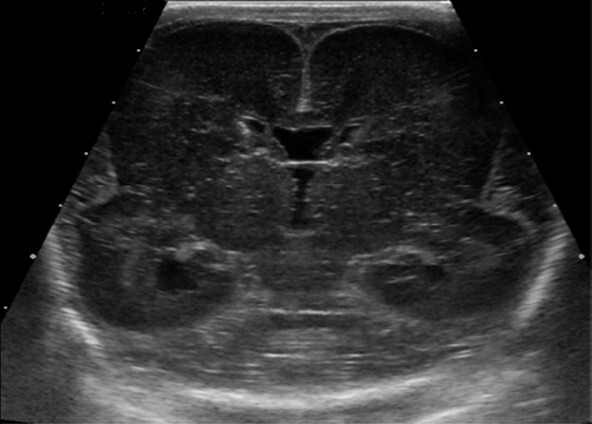

Neonatology Lissencephaly Image